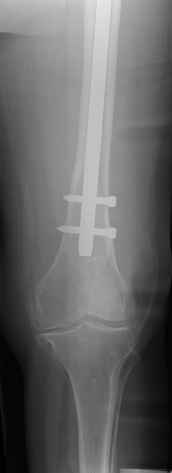

I should like know what is your preferred treatment for this fracture at

the tip of a long Gamma nail (on a healed subtrocantheric fracture : see

img).

The patient is a 81 years old lady with osteoporosis and important knee

arthrosis (as you can see).